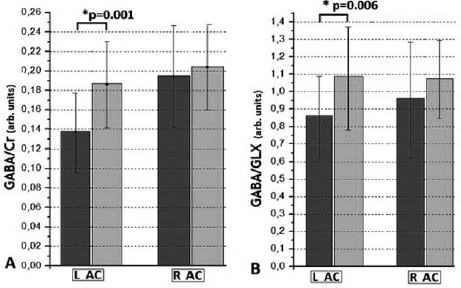

Fig. 2 Reduced GABA (A) and GABA/GLX (B) in the left ACC.

The main effects on the GABA/Cr (t[45] = 4.17, P < 0.01) (Fig. 2A) and GABA/GLX (t[45] = 2.84, P < 0.01) (Fig. 2B), were found in the left ACC (t[45] = 4.17, P < 0.01), with the patients having lower GABA/Cr and GABA/GLX ratios as compared to the control group. Also significant negative correlation (r = −0.49, P = 0.04) between GABA/Cr in the right ACC and the current daily dosage of antipsychotic medication in CPZ-Eq was found (Fig. 3).

This study reveals for the first time a significant reduction of (GABA) (25%) and GABA/GLX ratio (20%) in left AC of UHR subjects. According to (de la Fuente-Sandoval, Int J Neuropsychopharmacol 2015;19[3]) and association of (GABA) with daily dosage of medication found, this reduction may be caused by the antipsichotic treatment.

Fig. 2 Reduced GABA (A) and GABA/GLX (B) in the left ACC.

Fig. 2 Reduced GABA (A) and GABA/GLX (B) in the left ACC.